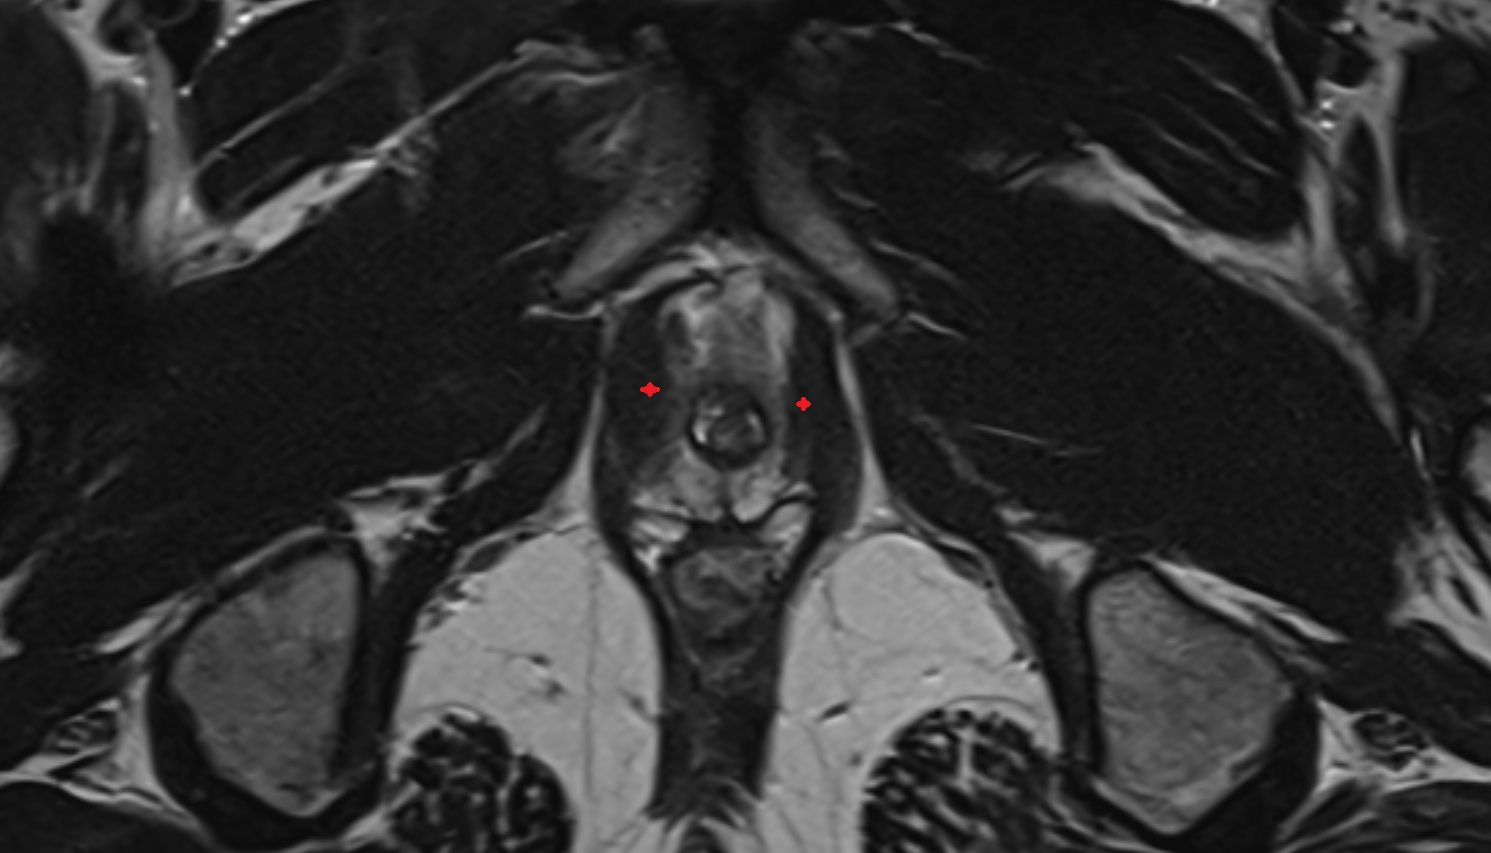

- Peripheral zone of prostate

- Anterior Fibromuscular Stroma of prostate

- Central zone of prostate

- Transitional zone of prostate